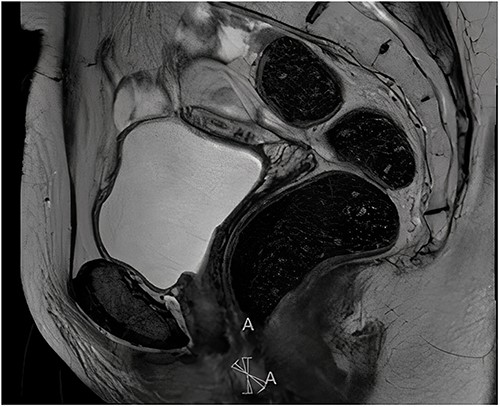

Histopathological examination of the biopsy showed an adenocarcinoma metastasis of rectal origin. A full body positron emission tomography (PET)-scan and MRI were made and confirmed the vaginal lesion of 1.7 × 1.4 × 1.5 cm located in the posterior wall of the vagina just above the puborectal sling (see Figs 1 and 2). From the histopathological and imaging diagnostics we concluded that the patient had a distal rectovaginal septum metastasis of rectal origin.

Axial view of diagnostic MRI-rectum with the solid tumour indicated with the linear mark ‘A’.